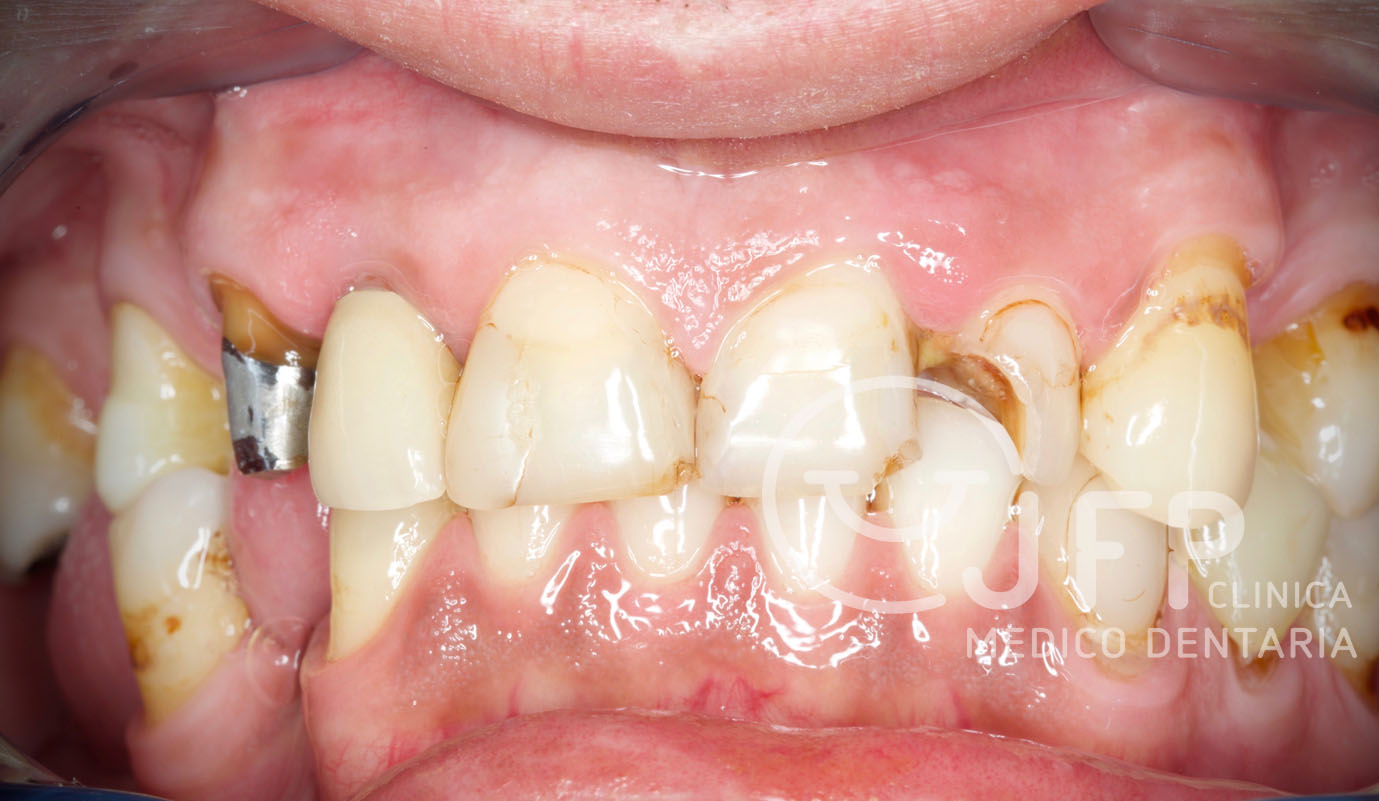

A reabilitação oral protética é compreendida por várias etapas sendo todas elas importantes. A chamada “fase de provisórias” tem muitas vezes mais relevância do que as restantes, para o diagnóstico, planeamento, tratamento em si e para a fase de manutenção. A etapa das provisórias faz parte do início da fase terapêutica, mas espelha todo o planeamento pensado e executado para cada caso clínico e posteriormente o grau de motivação e compromisso esperado na fase de manutenção pelo paciente.

Sobre dentes naturais colocam-se as peças de cerâmica (coroas ou facetas) feitas em Laboratório, a partir de um molde tirado ao dente original. Antes da peça ser colocada sobre o dente, este sofre uma ligeira preparação para que a esta possa ser devidamente aderida ao dente original. Com este tipo de tratamento é possível mudar a cor, a forma, a orientação, o tamanho e mesmo o comprimento dos dentes. Resolvem-se problemas como:

- Melhorar a aparência dos dentes quebrados ou danificados por cáries;

Casos de prótese fixa sobre dentes